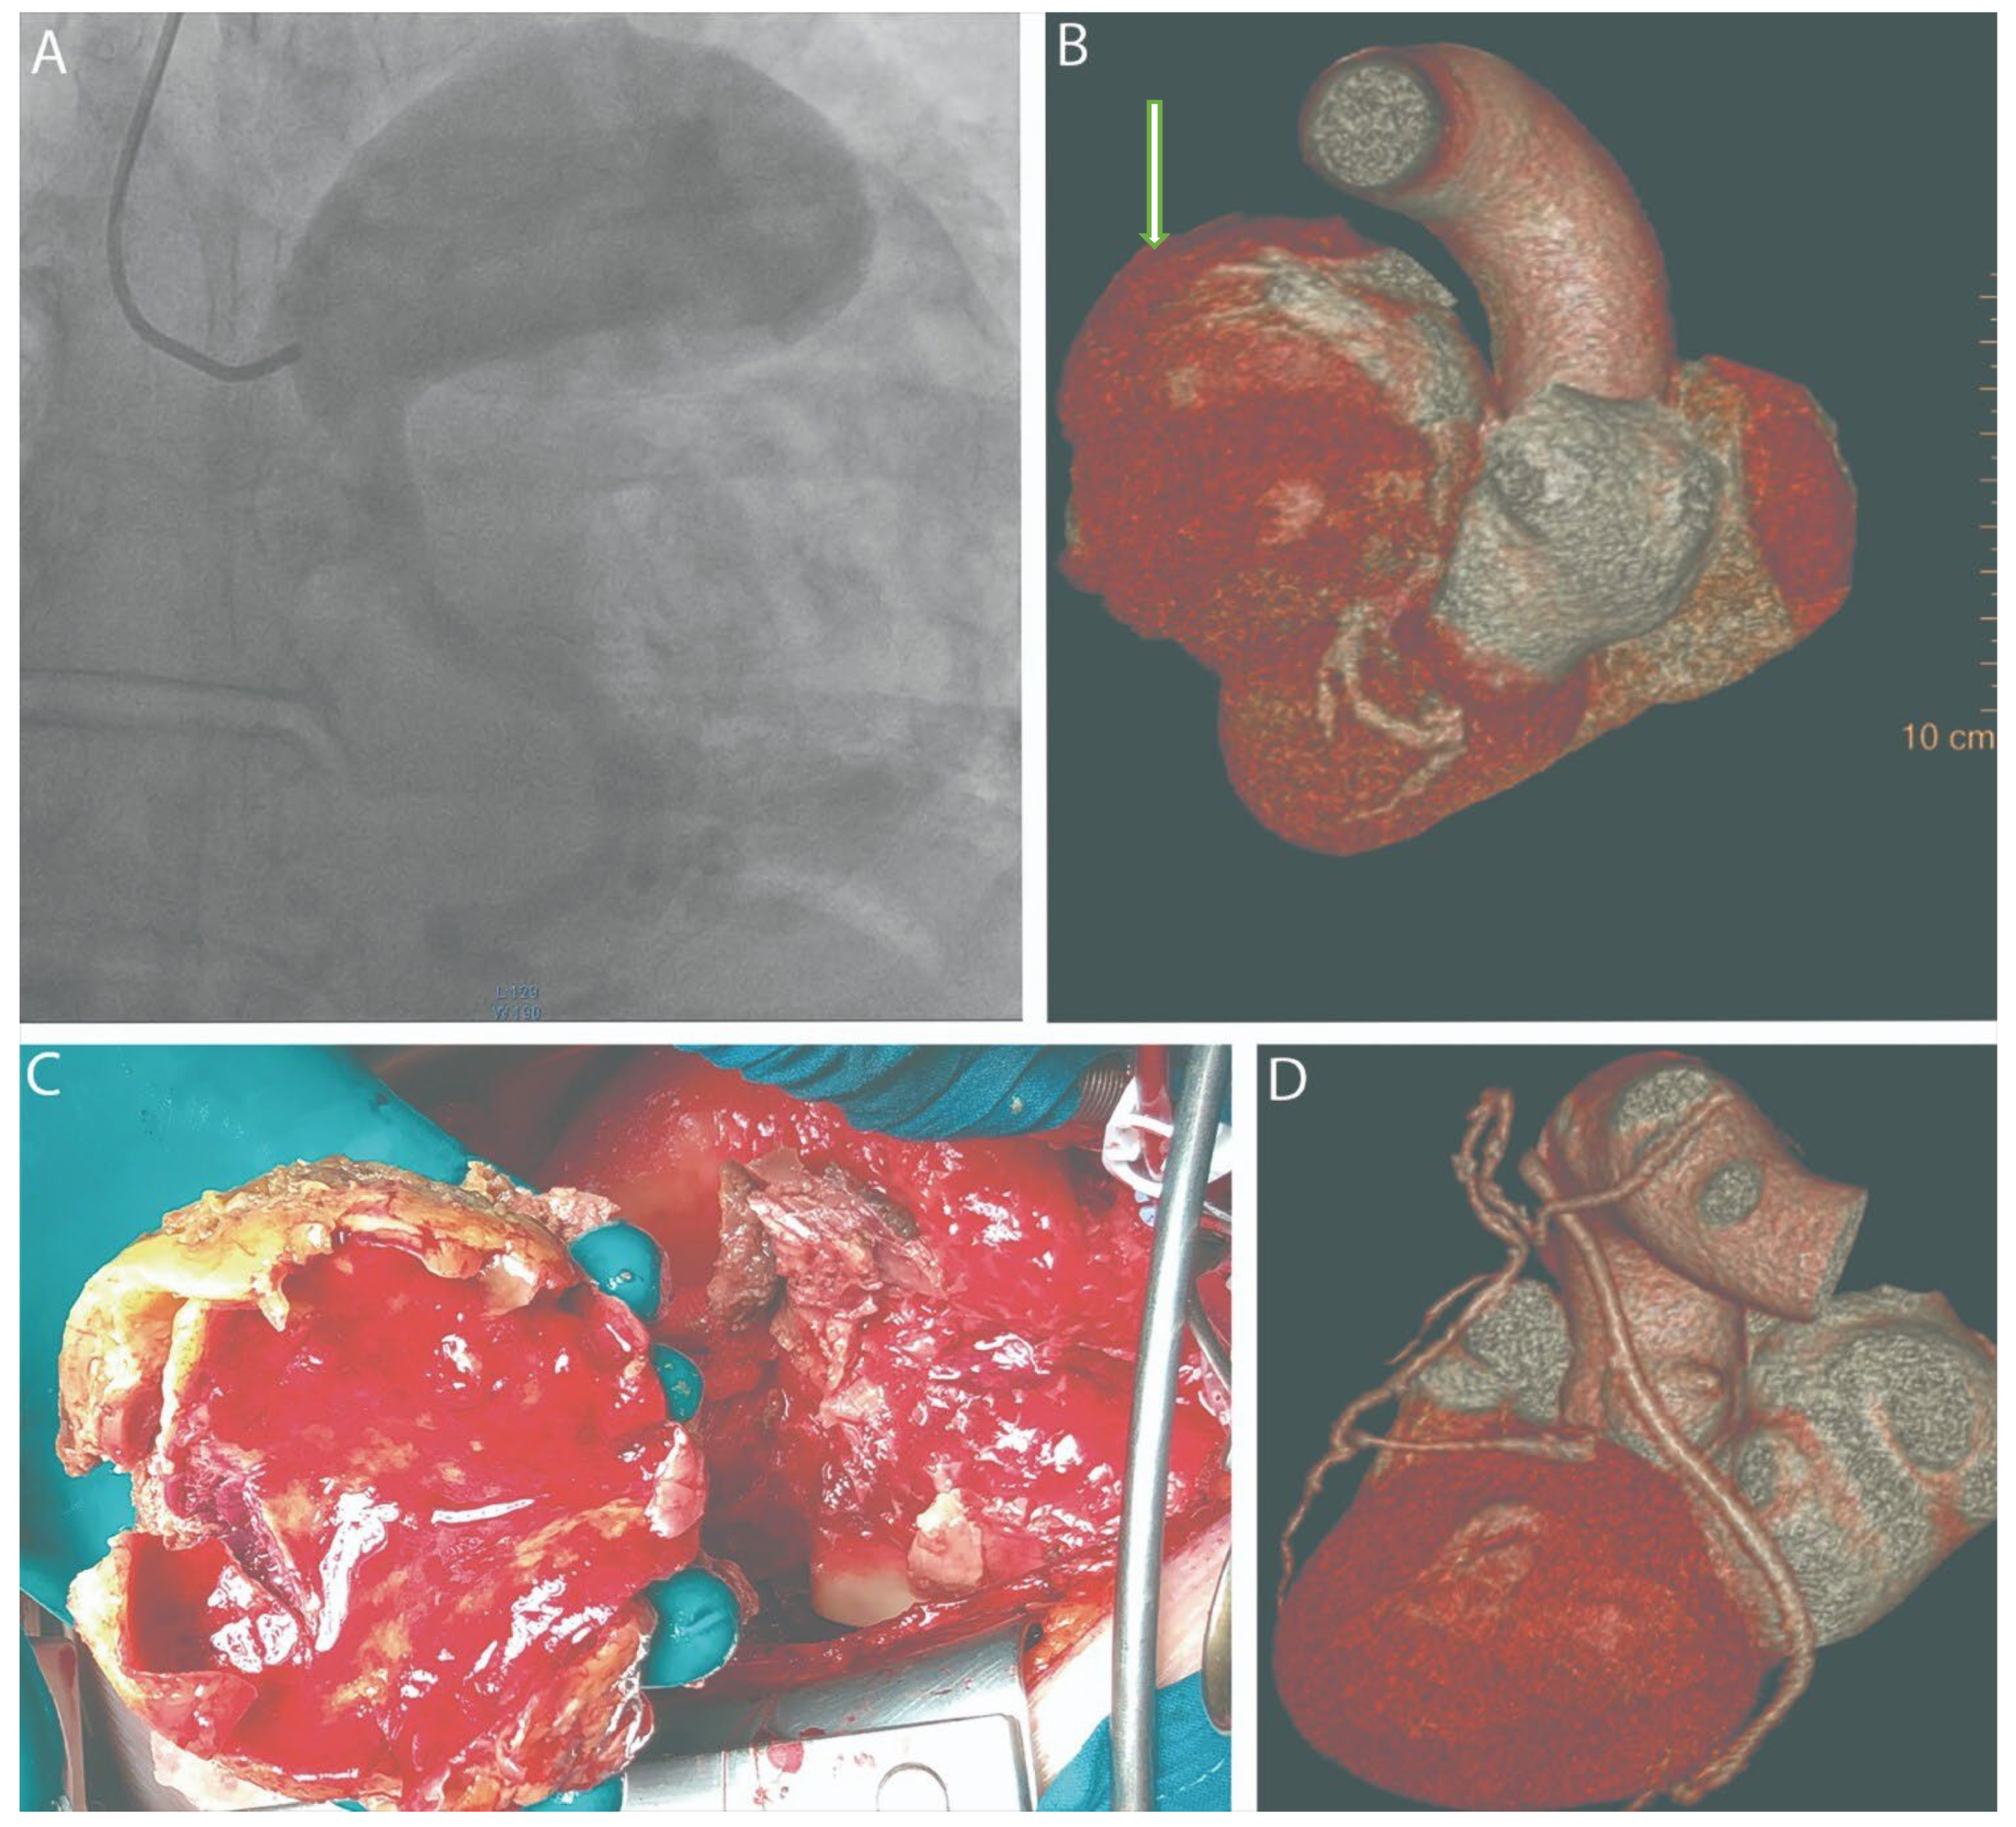

Shumakov, D.; Zybin, D.; Stepanova, E.; Dabravolski, S.; Sigaleva, E.; Silina, E.; Stupin, V.; Popov, M. Surgical Management of a Ruptured Giant Left Main Coronary Artery Aneurysm Presenting with Cardiac Tamponade. Diagnostics 2025, 15, 2302. https://doi.org/10.3390/diagnostics15182302